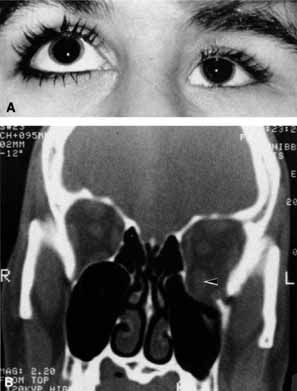

Optociliary shunts (Fig. 12A) develop as a result of long-term obstruction of the central retinal vein. This may occur secondary to optic nerve meningiomas,13 optic nerve gliomas,14,15 optic nerve meningoceles,16 central retinal vein occlusions,17 optic nerve sarcoidosis,18 craniosynostosis,19 optic nerve arachnoid cysts,20 optic disc drusen,21 and papilledema.15 Congenital optociliary shunts, which are exceedingly rare, have not been associated with optic neuropathy or orbital disease.22,23 The presence of optic nerve pallor, poor acuity and optociliary shunts generally implies an optic nerve meningioma in the absence of other funduscopic findings (Fig. 12B).13

Fig. 12 A. Optociliary shunt vessels (arrow) are present on the surface of an atrophic optic disc. The patient's visual acuity was hand motions. The patient demonstrates 2 mm of proptosis. B. Gadolinium-enhanced, fat-suppressed magnetic resonance imaging (MRI) demonstrates an intraorbital optic nerve sheath meningioma (arrow).